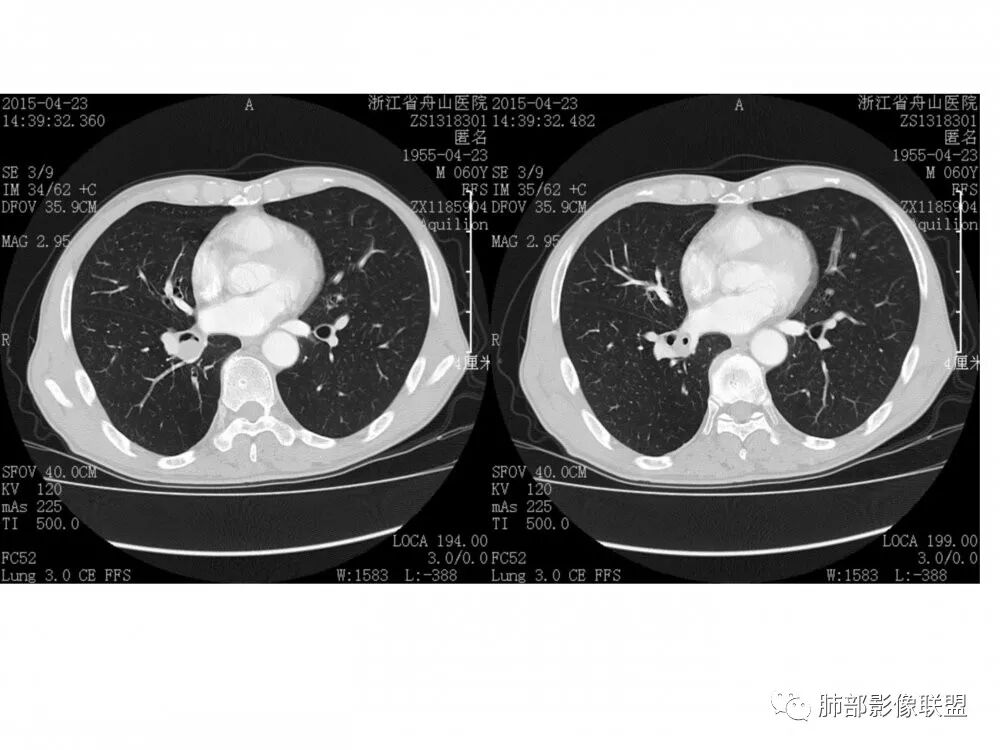

右肺下叶基底段支气管旁结节,低强化,支气管受压变窄,软骨连续未见破坏,右肺门及纵隔多发淋巴结增大,低强化与结节强化一致,考虑小细胞肺癌可能

右肺门结节,内见包埋血管,不均匀强化,长轴沿支气管且围绕支气管生长,支气管受压狭窄而未阻塞,肺门及纵隔见肿大淋巴结,老年男性,似有肺气肿背景,考虑恶性肿瘤性病变,首选小细胞肺癌

右下肺支气管粘膜下肿块,有中度强化,有阻塞气管征象,纵隔多发肿大淋巴结,考虑恶性,并淋巴结转移,小细胞>鳞癌,

老年男性,右肺下叶支气管腔狭窄,见低强化软组织密度结节突向腔内,局部支气管壁破坏消失,邻近血管受压推移,纵膈内及右肺门区淋巴结肿大。综合考虑小细胞肺癌(SCLC)可能性大,鉴别类癌及鳞癌。

老年男性,右肺下叶支气管开口新生物,基底干及中间支气管受累狭窄,支气管管壁破坏明显,强化低,不均匀,肺门、7组、4R淋巴结肿大,考虑恶性支气管腔内肿瘤,小、鳞可能大,需与类癌、粘表等鉴别。